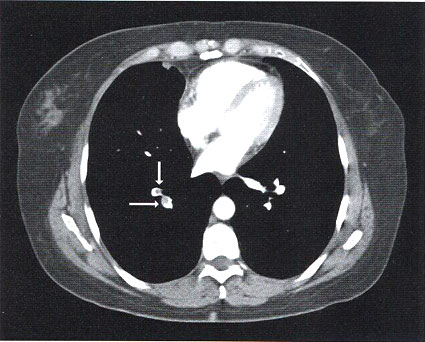

Questo è il referto: “..in riferimento al quesito clinico, si evidenzia singolo difetto di riempimento a carico di ramo sub segmentario del lobo inferiore di destra …. Si segnala inoltre addensamento con broncogramma aereo a carico del lobo inferiore di sinistra in sede posteriore ….”

Ecco spiegato. Febbricola, tosse, ipossiemia, indici di flogosi elevati, terapia cortisonica protratta… la signora ha una polmonite. Effettivamente non ho scandagliato il torace posteriormente … non ne voleva sapere di mettersi seduta … e probabilmente l’unica proiezione AP del torace con mascheramento da parte dell’ombra cardiaca non ci ha permesso di vedere l’addensamento. Ma quel singolo difetto di riempimento sub segmentario? Devo anticoagulare la paziente? Di sicuro non c’entra nulla con il corredo sintomatologico attuale. Quindi la ricovero in medicina e che ci pensi l’internista!

Diagnosi di ricovero: “POLMONITE BASALE POSTERIORE SINISTRA. EMBOLIA POLMONARE SUBSEGMENTARIA (SINGOLO DIFETTO)”